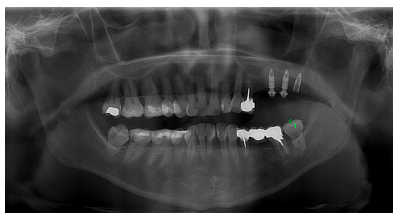

A los tres meses, se solicitó un control radiográfico mediante radiografía panorámica observándose una correcta osteointegración de los implantes (Figura 13), por lo que se derivó a su prostodoncista para la rehabilitación de estos.